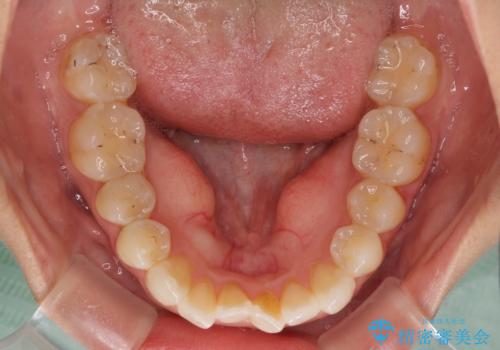

- 中学生の時に矯正治療をしたものの、後戻りを気にして来院された患者様です。

骨格的に下顎が右側に変位しているため、左右の咬み合わせを理想的なものに改善することはできませんが、インビザラインにて歯列を整えることとしました。

骨格的なズレによる左右差は改善できませんでしたが、上下の正中を極力合わせるようにすることができました。